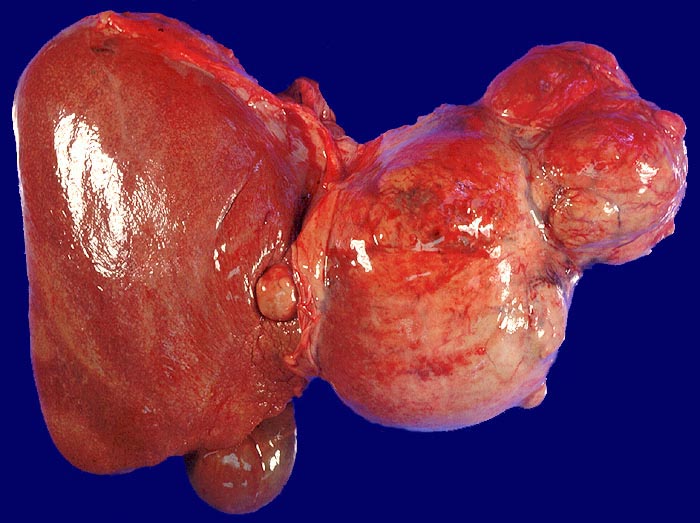

Morphologie: Makroskopisch imponiert das hepatozelluläre Karzinom als solitäre grosse Tumormasse, als zahlreiche zirrhoseartige Knoten oder als scharf begrenzter Knoten mit oder ohne Kapsel. Die tumorfreie Leber ist in der Mehrheit der Fälle zirrhotisch umgebaut. Mikroskopisch bilden die Tumorzellen mehr als 2 Zellen breite Trabekel ( 1237), kompakte Tumormassen ( 1229) oder pseudoglanduläre Strukturen (dilatierte Canaliculi) ( 1212)( 1199). Desmoplastisches Bindegewebe fehlt meist. Innerhalb des Tumors fehlen Portalfelder. Es finden sich lediglich Arterien. Etwa bei der Hälfte der Karzinome lässt sich intrazytoplasmatische oder intracanaliculäre Galle ( 1238) nachweisen. Immunhistochemisch lassen sich mit einem polyklonalen Antikörper gegen Carcinoembryonales Antigen (CEA) Gallecanaliculi zwischen den Tumorzellen nachweisen. Die Tumorzellen bilden keinen Schleim.